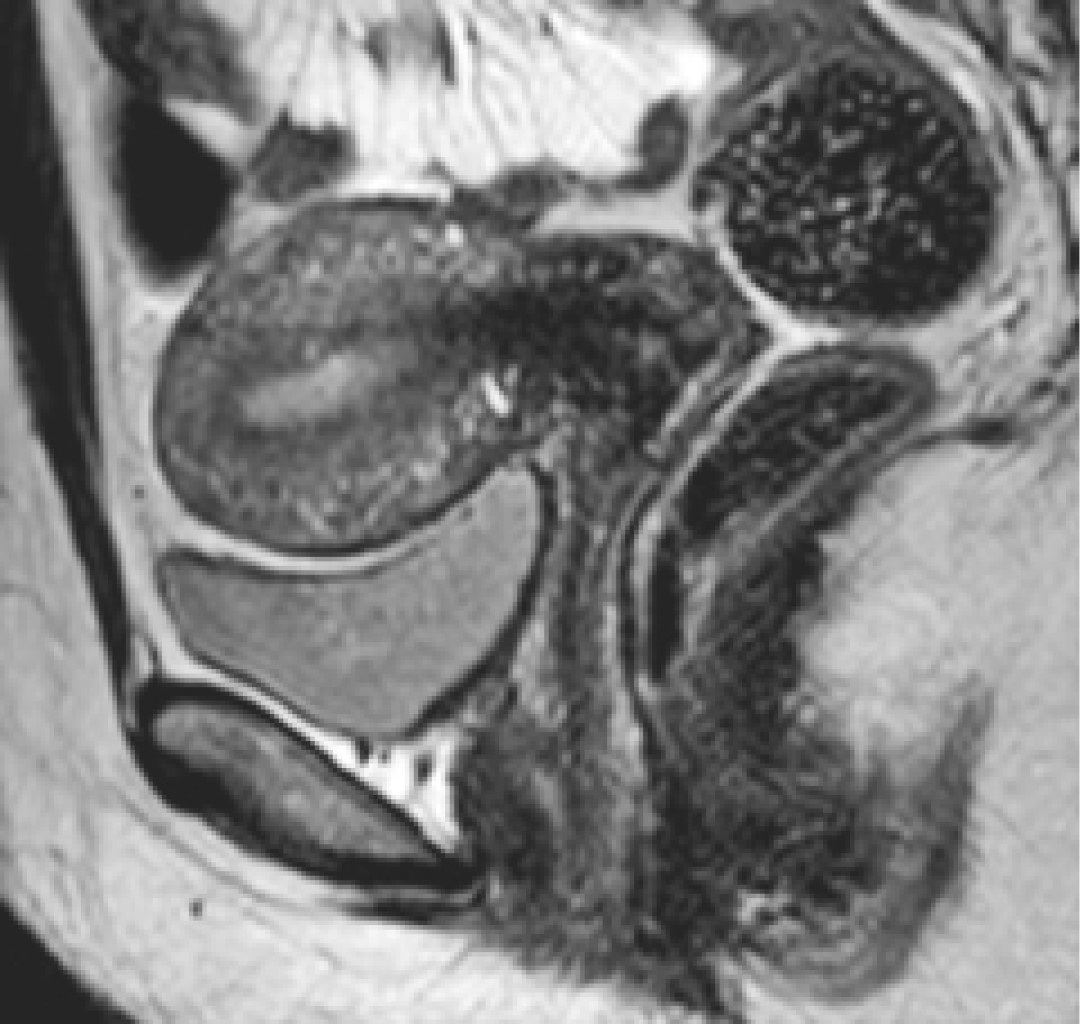

Adicionalmente, los hallazgos por resonancia magnética pueden ser clasificados como signos directos o indirectos. Dentro de los directos se encuentran los microquistes, siendo éstos el principal signo de adenomiosis identificable por resonancia magnética, los cuales tienen un tamaño de entre 2-7 mm, con una media de 3 mm y se encuentran dentro del miometrio (Figura 3),10 además de que se hallan principalmente en la zona de unión y raramente en el miometrio; son hipointensas en T1 e hiperintensas en T2, e identificables de mejor manera al final del periodo menstrual con cavidad quística.11 Los adenomiomas que se encuentran como una consolidación focal de las glándulas adenomióticas dentro del miometrio se manifiestan como una masa de paredes bien delimitadas en la zona de unión, por lo que el principal diagnóstico diferencial es el leiomioma uterino, ya que ambas presentan el mismo grado de intensidad, con la única diferencia que la vascularidad de los adenomiomas presenta más angiogénesis (Figura 4).12

Figura 3